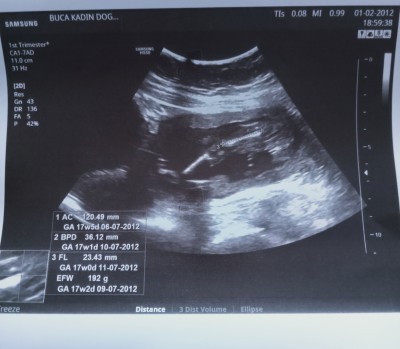

cinsiyet tahmini yapabilen varmı

16.4

Bacak kemiği ölçülmüş ve kızınız 1 hafta önden gidiyor

kız nerden anladın

Pipi yok iki oğlum var ultrasonlarında hemen gördüm